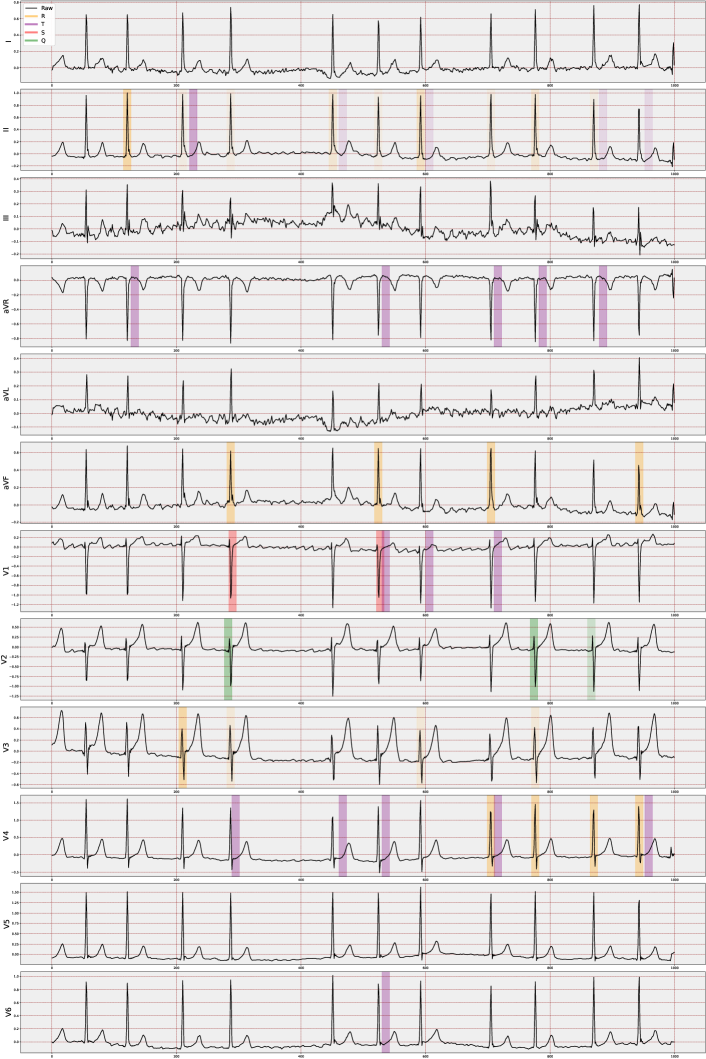

4.3 VCCE: Visualizing Counterfactual Clues on Electrocardiograms

We have developed a visualization method, VCCE, to enhance the presentation stage of the obtained counterfactual clues to the end-user, i.e., the clinician. This structure involves highlighting counterfactual clues obtained from the patient’s signal in the ECG report. For visualization, we offer various options that allow the display of peaks in chosen regions along with advanced features. These features are computed via amplitude differences and are presented as lines with their distance values overlaid on the ECG signal. Moreover, when visualizing counterfactuals, the more a specific feature is selected in an alternative world, the more it is strongly highlighted on the ECG report.

In essence, this approach, may adaptable independently of the ECG task, enables us to observe changes in PQRST across many “possible worlds," providing a means to perceive alterations across different scenarios. The main justification for assuming the applicability of VCCE across a wide range of ECG tasks is fundamentally rooted in the nature of the employed ECG features, similar to other ECG-dependent cardiac conditions. These features are extracted based on the structure of the P-, Q-, R-, S-, and T-waveforms (cardiac cycle) at a beat level, which remains a consistent term across all ECGs. The key advantage lies in the fact that these derived features offer distinct temporal and amplitude-level information that is inherently interpretable. Consequently, we can not only numerically analyze the generated counterfactual scenarios but also precisely determine their impact on specific waves within particular leads and beats.

In the proposed study, we note that the selected top 20 features are predominantly non-temporal due to their dependence on lead-wise amplitude characteristics across all MI cases in the dataset, with RR_Next being the only temporal one. Therefore, our visualization method primarily focuses on amplitude-based (non-temporal) features. Additionally, we have included four more features, selected by domain experts, to enhance individual resolution, such as distinguishing between inferior and anterior case differences. Consequently, we initiate a decoding process to unfold the temporally compressed beats. This decoding involves expanding the feature names to indicate the specific area influenced by the counterfactuals responsible for the change, encompassing details such as the lead, the waveform feature, and the beat associated with the counterfactual’s impact. This way, we are individually marking the features that contribute the most significant distinction between the two diagnoses.

5.3 Visualization of Counterfactual Clues

Understanding changes solely based on ECG features remains a time-consuming process within generated scenarios. Integrating simplified visualizations could effectively improve the grasp of pertinent indicators. To evaluate both the generated clues and the complete ECG report, we adopted custom measurement techniques. These measures involved assessments by expert cardiologists, incorporating both blind evaluations and interactive appraisals. This strategy improved the comprehensive evaluation of the generated clues.

In addition to the analysis in Section 5.2, our preliminary empirical investigations on visual assessments have led domain experts to conclude that the incorporation of four additional features (V2_T, V3_T, V4_T, and V6_T) can be both beneficial and necessary. These features have not only enhanced the quality of visualization but also improved the classification accuracy. This was evident in the identification of local MI cases, such as case ID 3234.0 in the dataset, where the system accurately identified 6 out of 7 individual beats, compared to the previous 2 out of 7.

51 reports were evaluated (Figure 5); 5 of them were excluded due to extreme artifacts (n=1, =0) and ventricular extrasystole (n=4, 10.25 ± 5.5). Of the remaining 46 reports, 17 were categorized as high (23.29 ± 1.04), 14 as moderate (20.28 ± 0.99), and 15 as low (11.20 ± 7.76) in terms of interpretability. The "±" symbol represents the mean and standard deviation of validation scores, respectively. A total of 31 reports were identified as acceptable.

The Figure C.2 illustrates the distribution of raw and denoised signals across various leads for a selected beat within the population. It is important to note that individual investigations might encounter significant noise, and this figure serves as an example to showcase the substantial variance in beats across the population. Moreover, the figure visibly demonstrates the considerable discrepancy in signal amplitude values between the NORM and MI populations.

The effect of denoising on one beat is demonstrated for two random samples in Figure C.3. Moreover, in Figure C.4, we can also observe how the signal in each lead changes discretely for the samples.